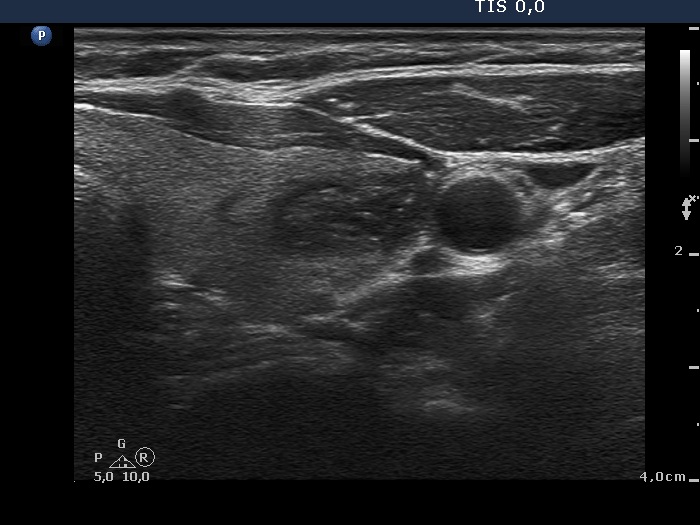

Ultrasonography. The thyroid was echonormal. There was a minimally-moderately hypoechogenic nodule in the right while a cystic nodule in the left lobe. There were numerous hyperechogenic figures both in the cystic and in the lower solid part of the lesion. The lesion presented no vascularization.

Comment. The presentation of the bright hyperechogenic granules are relatively unusual, they were mostly located within the solid part causing a false impression of starry sky phenomenon. In fact, they were comet-tail artifacts.